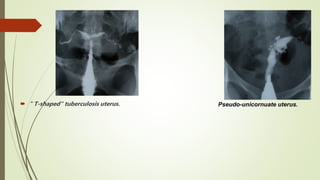

 " T-shaped" tuberculosis uterus. Pseudo-unicornuate uterus.

Indentation of thecavity due to synechiae

 " T-shaped"tuberculosis uterus. Pseudo-unicornuate uterus.